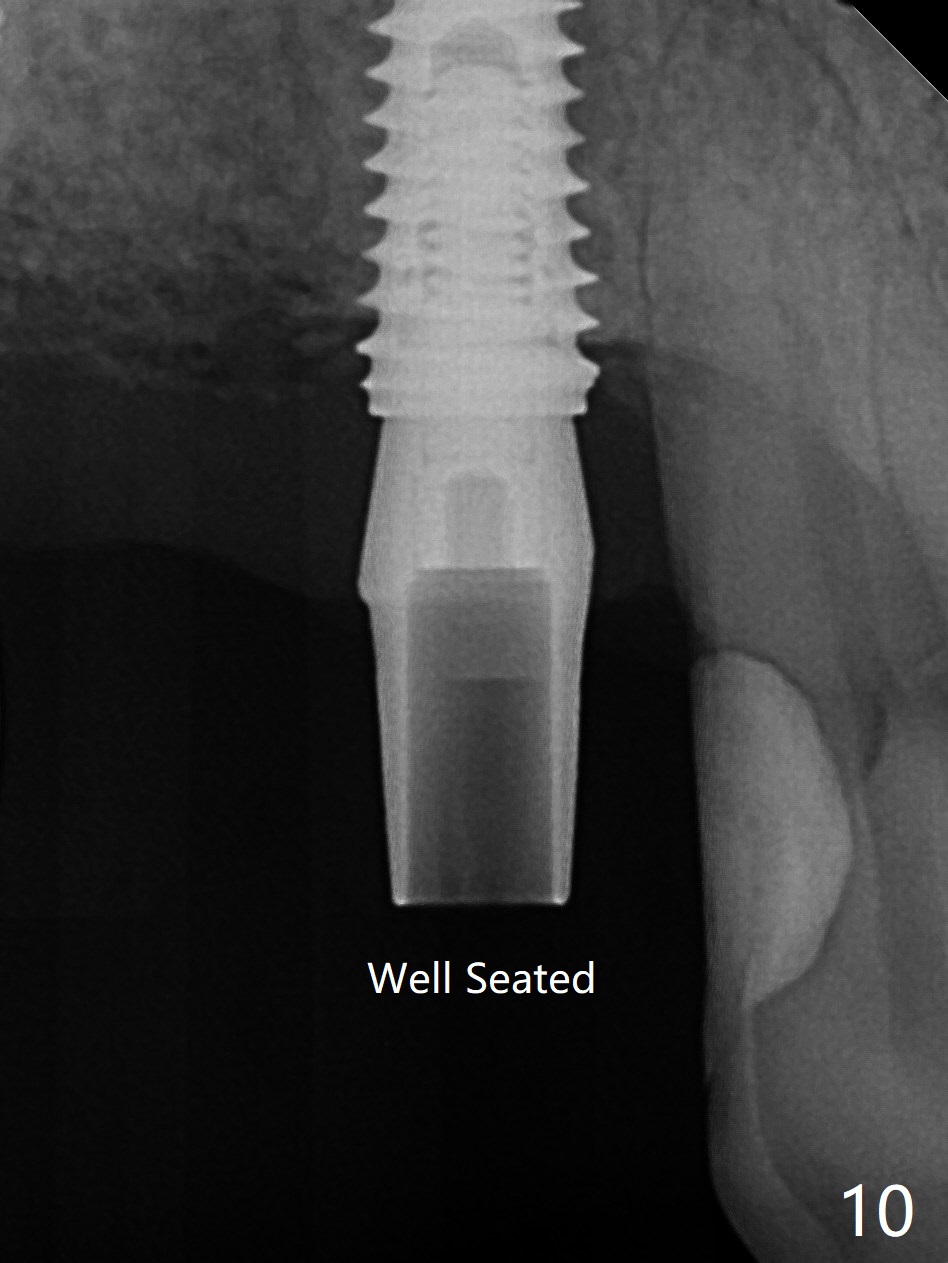

Today schedule is to extract the teeth #4 and 5 and place an implant at #5. When the latter is done, it appears that the implant at #15 should be placed at the same appointment (Fig.1). Once an abutment is placed at #5 (Fig.2 A, 5) for temporary crown (Fig.4 T) , the guide may be not seated again unless the crown is removed. Luckily the implant placement at #15 is quick and smooth with the guide (Fig.3,6). The implants seem to be covered by the bone 4 months postop (Fig.7,8). #15 abutment screw needs retightening because of long crown 1.5 months post cementation. Access hole is palatal. There is premature contact in lateral movement. The buccolingual occlusal table is large at #14 and 15. In fact there is more occlusal contact at #14 than #15 in centric occlusion. Tissue level implants should have been placed to reduce implant/abutment loosening. The incomplete abutment seating (Fig.5,7) is noted after retightening the loose cantilever FPD 1 year post cementation (Fig.9 <). After removal of the FPD, the abutment is reseated completely without interference of the proximal contacts (Fig.10).